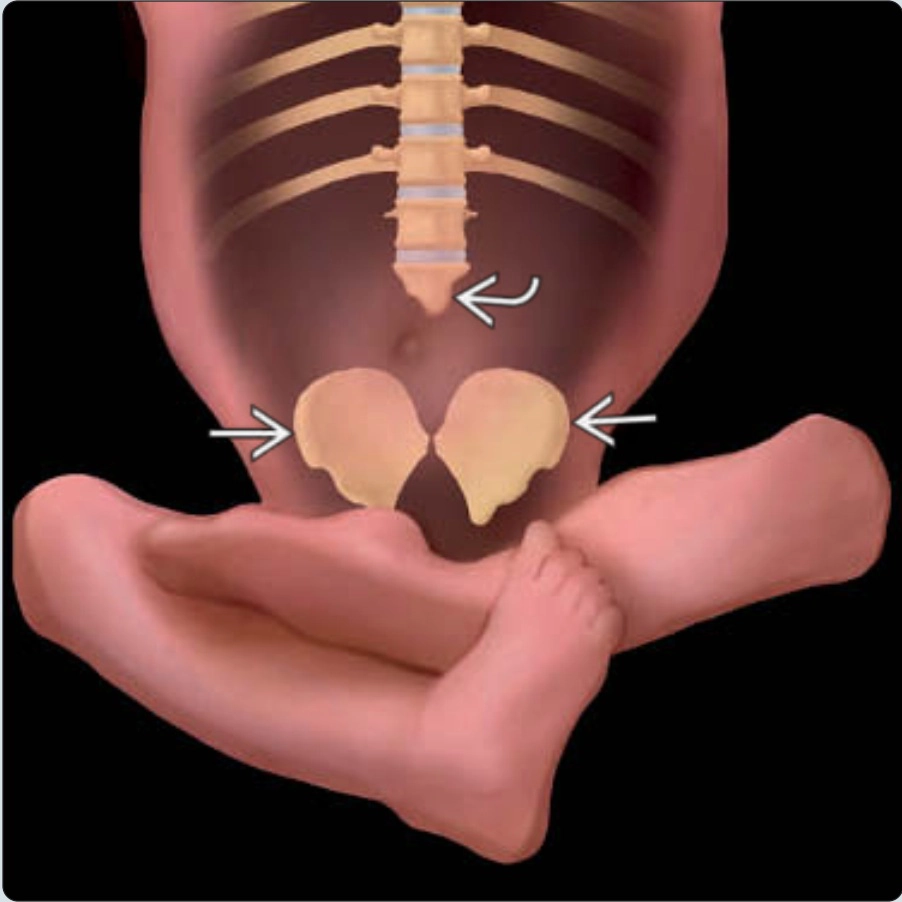

Thoái hóa cột sống bẩm sinh (Caudal Regression Sequence)

• Thoái hóa cột sống bẩm sinh (Caudal Regression Sequence)